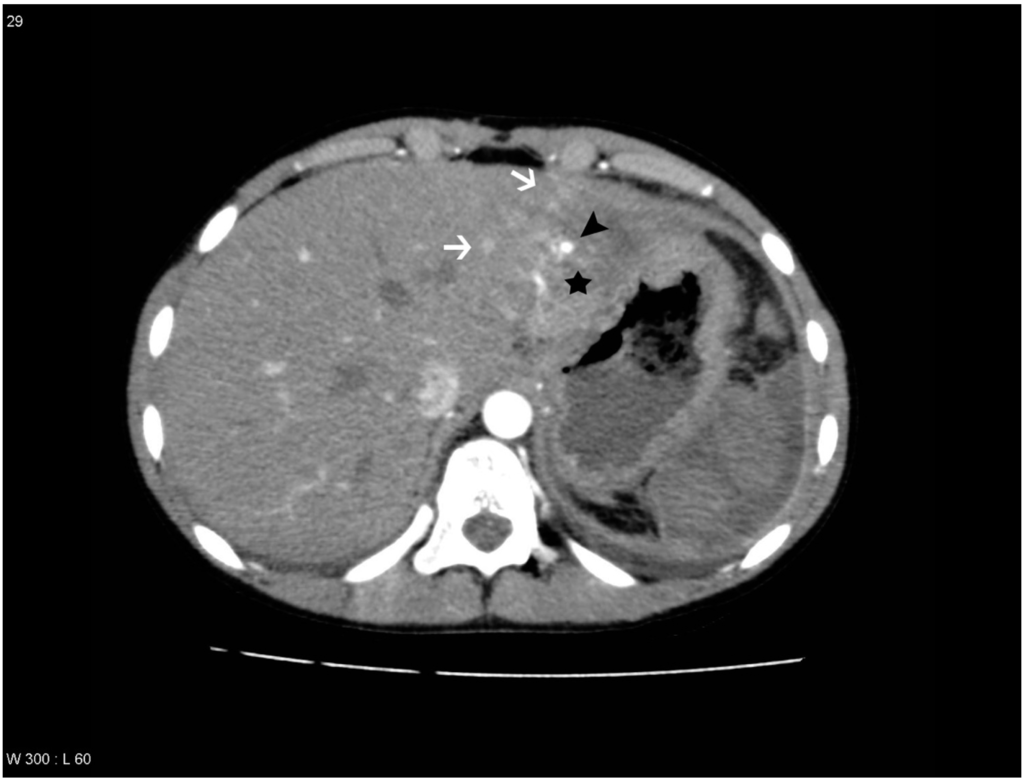

Figure 1. Patient with a pseudoaneurysm within the liver lesion in segment 2, which was confirmed by digital subtraction angiography (DSA) and treated with embolization. Areas with transient hepatic attenuation difference (THAD) surround the lesion. The liver lesion is marked with a black star, the areas with THAD are marked with white arrows and the pseudoaneurysm is marked with a black arrowhead.

PS/AF can be recognized and distinguished from THAD by the location, the appearance, and the HU level. PS/AFs seen in 14% of the patients were all oval or round except one, which was linear, and all had focal enhancement with mean HU levels of 170. All PS/AFs were found within the liver lesions (Figure 1 and Figure 4). PS and AF were indistinguishable as stated previously by others [9]. Areas with THAD seen in 54% of the patients had hazy borders, were all found in the periphery of the lesion and with mean HU levels of 100 (Figure 1, Figure 2, Figure 3 and Figure 4).